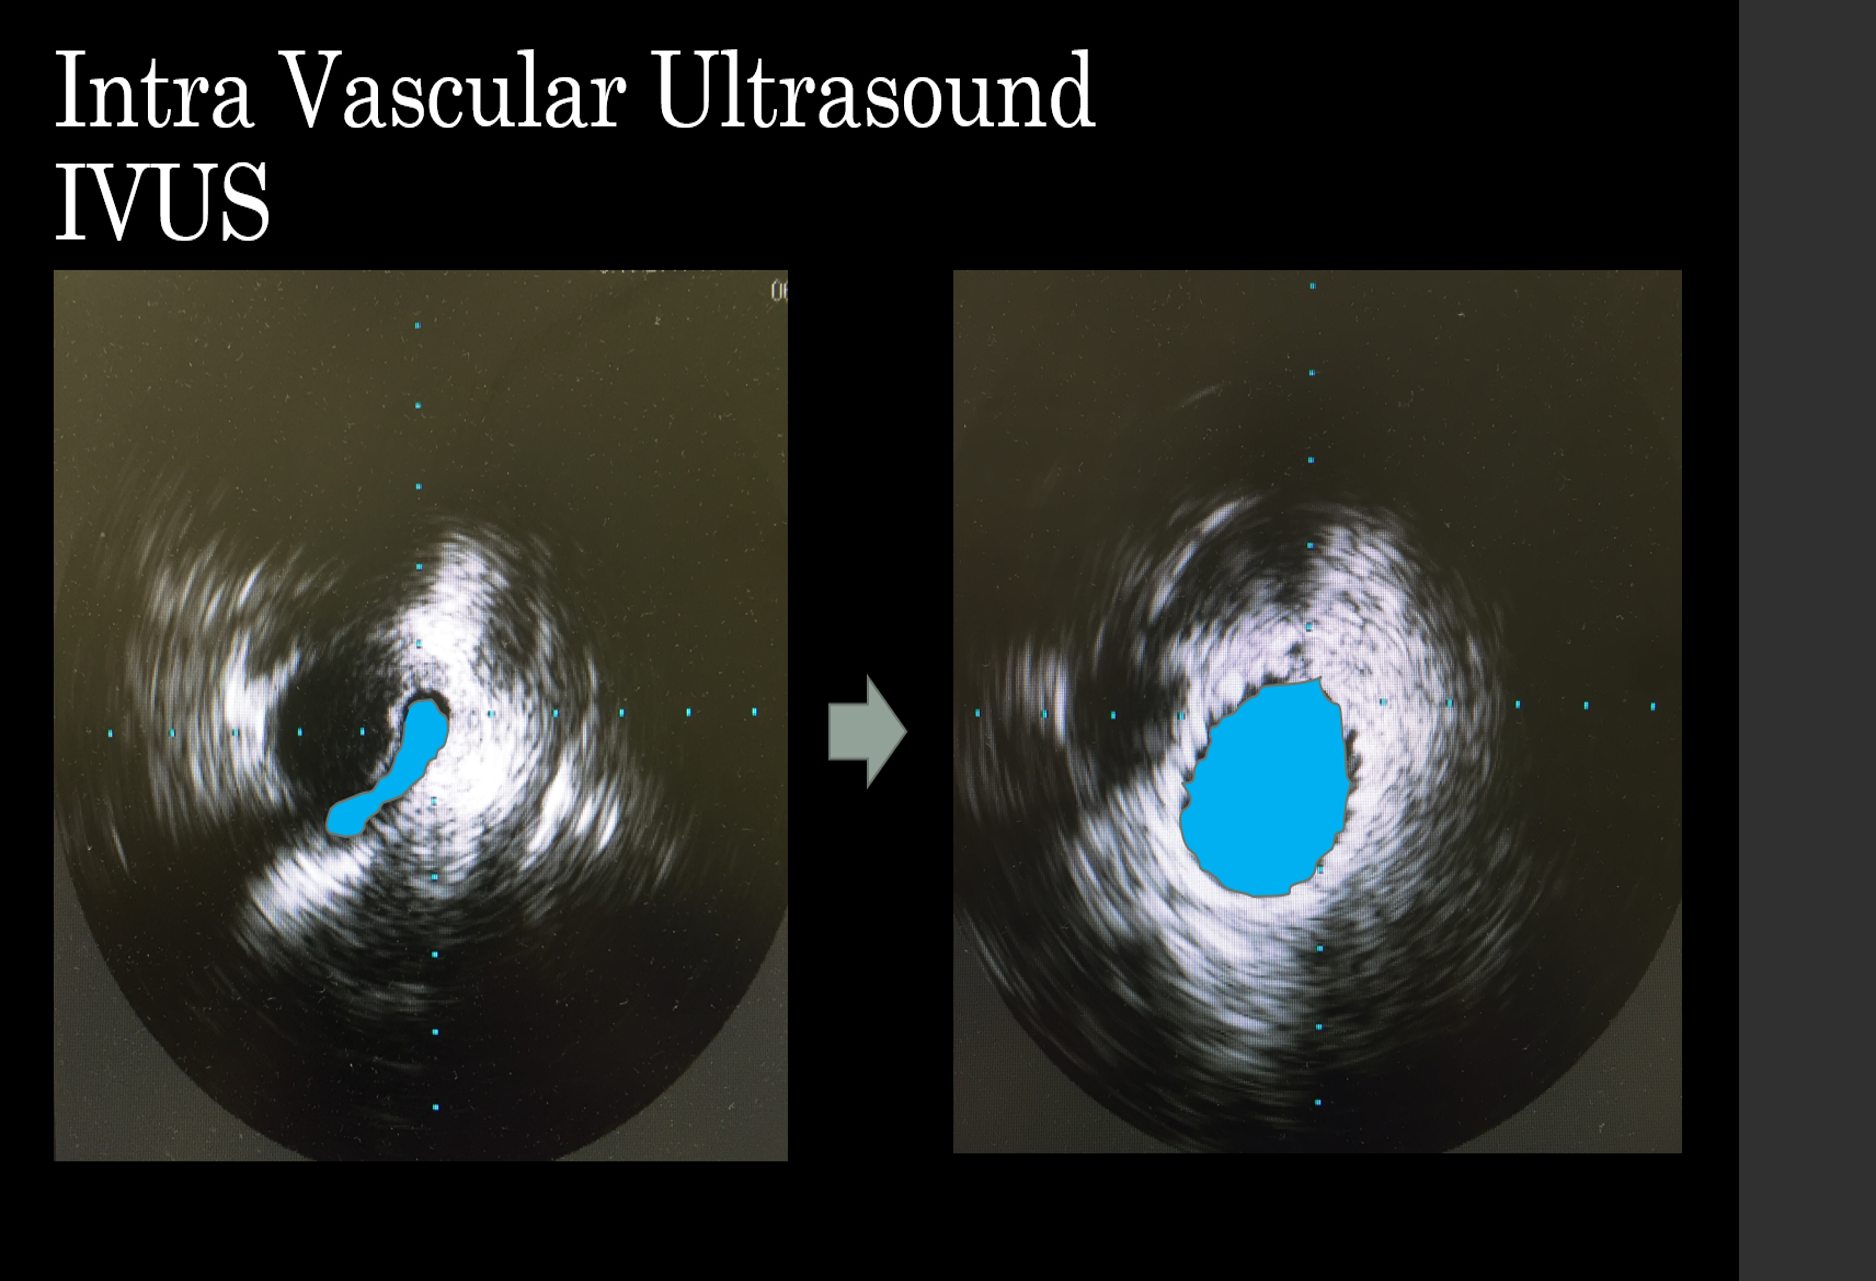

Intravaskulární ultrazvuk (IVUS) je schopen bezpečně rozpoznat zůžení v žíle a umožnit chirurgovi v téže době žílu opravit. Na levém obrázku je vidět , jak byla pánevní žíla významně komprimována a po perkutánní plastice došlo k jejímu zvětšení (modrá).

Takový výkon je možný bez chirurgického řezu, pouze za použití vpichu (vpravo).

Diagnostika a léčba žilních chorob zaznamenala dramatické změny, a to zejména pokud jde o pochopení patofyziologie. Výrazně se zlepšila diagnostika díky použití miniinvazívních katetrizačních přístrojů (IVUS, intravaskulární ultrazvuk). Výsledky rekonstrukcí uzavřených hlubokých žil v posledních deseti letech jsou v takových centrech velmi dobré a proto odborníci, kteří mají zkušenosti s takovými operacemi jsou dnes schopni nabídnout svým pacientům zlepšení kvality života a přitom je bezpečně propustit z nemocnice následující den po výkonu s návratem do běžného života v několika dnech.